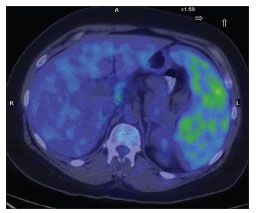

Positron emission tomography/CT imaging was performed on day 8 of the patient's hospitalization, and the scan revealed abnormal, hypermetabolic activity within the enlarged, heterogeneous spleen (Figure 2). The rest of the scan was essentially unremarkable. The splenic lesions were considered to be consistent with abscesses, fungal infection, or lymphoma.

Figure 2.Positron emission tomography/CT scan showing hypermetabolic activity within lesions of an enlarged, heterogeneous spleen. (Image courtesy of the department of nuclear medicine, New York Presbyterian Hospital–Weill Cornell Medical College.)